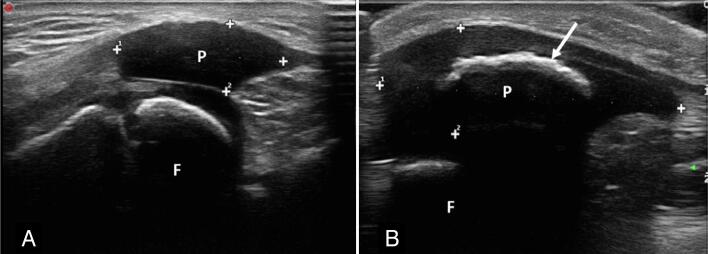

Objective: To analyze cases with clinical suspicion of patellar abnormalities, before ossification of the patella and to characterize the spectrum of abnormalities of the cartilaginous infantile patella by ultrasonography.

Results: Twelve patients with suspected patellar abnormalities were identified, with a mean age of 9 months and 4 days (±1.9 years), 75% male.

Findings: dislocation or subluxation associated with patellar hypoplasia (7 knees), low lying patella and patellar hypoplasia (2), unilateral patellar agenesis (1), bilateral patellar agenesis (1), patellar instability in dynamic assessment and absence of patellar morphological changes (1). In two patients, ultrasonography was negative. The craniocaudal diameter of the hypoplastic patellas measured 0.94 cm ± 0.24 cm and in the control group 1.24 cm and ±0.12 cm (p<0.01). The Insall-Salvati index adapted for ultrasonography measured 0.63±0.07 for the low lying patella and 0.93±0.16 in the control group (p=0.004).

Conclusions: Ultrasonography was useful to characterize abnormalities of the cartilaginous patella, and the most frequent findings were instability and hypoplasia. Level of Evidence IV; Case Series.